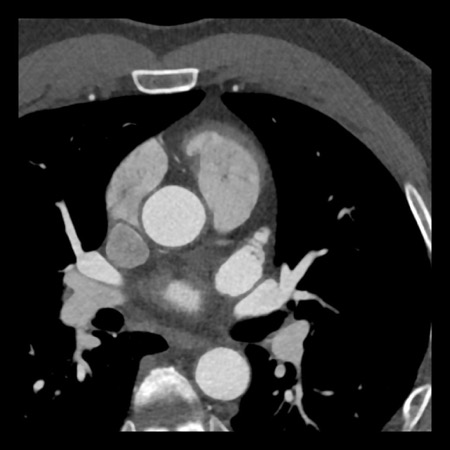

case 3 – Calcium score 0 and severe stenoses.

First, scroll through the CTA images.

How would you describe the findings on the coronary CTA?

The findings are:

- The total calcium

score of 0 indicates the absence of calcified plaque in the coronary

tree. - Severe stenosis

(70-99%) in the mid LAD and D2 branch.